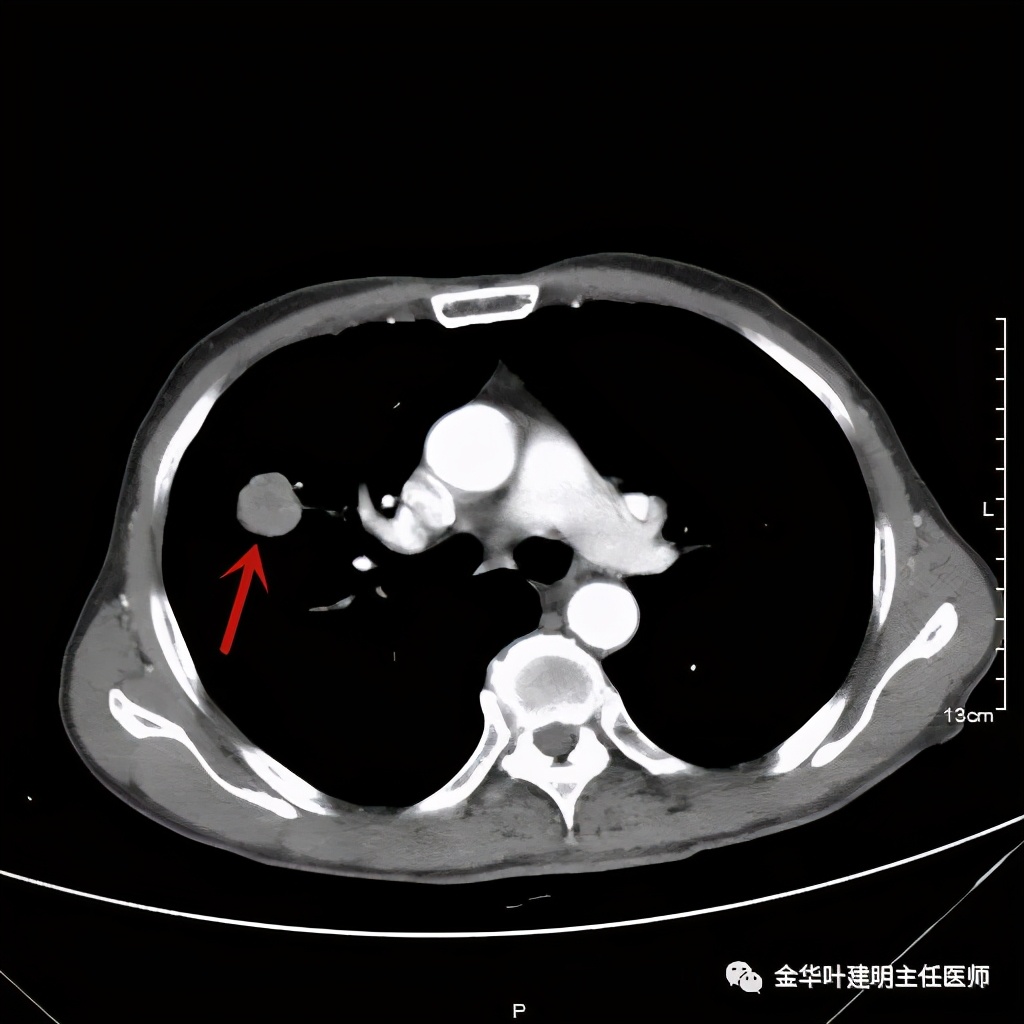

上图示纵隔窗病灶有膨胀性,内部有强化较明显的条索状(新生血管?)

上图示纵隔窗病灶表面欠平整,中间有小空洞,密度不均,局部似有坏死(空洞旁边)

上图示病灶内部有条索状的强化影,考虑是病灶内的新生血管可能性大

上图示病灶强化不等,表现不平,中间有空洞,空洞旁边有偏低密度区(坏死?)

上图示病灶膨胀分叶,表面不平,像个土豆

上图示病灶密度不均,有偏低密度的区域

上图黄色箭头示空洞形成,病灶表面不平